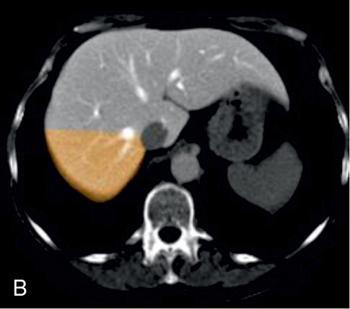

Ritu K. Kashikar, Shrinivas B. Desai Imaging is the mainstay of noninvasive diagnosis of the spectrum of abdominal pathologies or proving absence off thereof. Knowledge of normal anatomy and important normal variants is thus essential for the radiologist in order to avoid misinterpretation or erroneous diagnosis. This chapter highlights the normal anatomy of the hepatobiliary systems including the blood vessel and draining ducts and discusses relevant anatomical variants which may have important clinic implications. The liver is the largest abdominal organ, occupying the right upper abdominal quadrant and is in close approximation with the diaphragm, stomach and the gallbladder. It is largely covered by the costal cartilages. The liver is encapsulated by Glisson’s capsule which is a dense layer of connective tissue. It is covered by peritoneum, except in the regions of gallbladder fossa, fossa for inferior vena cava (IVC), and the bare area. The bare area is the posterocranial aspect of the liver, adjacent to the dorsal body wall, which is not covered by peritoneum. The liver has two surfaces, the convex diaphragmatic surface and a concave visceral surface. The slit in the hepatic hilum is called the porta hepatis and is penetrated by the right and left hepatic ducts (LHDs), hepatic artery and portal vein (PV). The distal portion of the lesser omentum is called the hepatoduodenal ligament and contains the common bile duct (CBD), hepatic artery, PV, nerves of liver and lymphatics. The liver has dual blood supply with hepatic artery providing 25% of hepatic blood and rest by portal vein (Fig. 9.2.1). Five ligaments connect the liver to the undersurface of the diaphragm. These include the falciform, the coronary and two lateral ligaments, all of which are peritoneal folds. The fifth ligament is a fibrous cord-like structure and represents the obliterated umbilical vein. The peritoneum invaginates into the liver parenchyma leading to formation of fissures. There are four normal fissures: fissures for the ligamentum teres, ligamentum venosum and gallbladder and the transverse fissure (Fig. 9.2.2). The liver is organized into microscopic functional units called lobules or acini. A central terminal hepatic venule surrounded by four to six terminal portal triads form a polygonal unit called the hepatic lobule. The terminal portal triad branches line the periphery of the unit. Between the terminal portal triads and the central hepatic venule the hepatocytes are arranged in one cell thick plates, surrounded by sinusoids. The blood flows from the terminal portal triad through sinusoids into terminal hepatic venule. Bile formed within the hepatocytes empties into terminal canaliculi which coalesce into the bile ducts (Fig. 9.2.3). This structure of the functional hepatic unit forms the basis of various functions of the liver. The normal relations of the liver are: The liver can be divided into right, left and caudate lobes. The right and left lobes are separated by the interlobular fissure and is oriented along a line passing through the gallbladder fossa inferiorly and the middle hepatic vein (MHV) superiorly (Fig. 9.2.4). This plane runs from the left of the IVC to the left of the gallbladder fossa and is a called the Cantlie’s line. Use of standardized, segmental anatomy is imperative because it facilitates communication and treatment planning. The segmental anatomy of liver is primarily based on vascular anatomy. The right lobe is divided into anterior and posterior sectors by of the right hepatic vein (RHV). The left lobe is divided into medial and lateraI sectors by an oblique plane connecting the left hepatic vein (LHV) and the falciform ligament. The liver is divided into upper and lower segments at the level of main portal vein (MPV) bifurcation (Fig. 9.2.5). Various systems are used in classification of liver anatomy. These are discussed in Table 9.2.1. The Couinaud’s system is the most commonly used and divides eight sections/segments which are discussed in details below (Table 9.2.2). 1. Segment 1 – Caudate lobe Bounded anteriorly and medially by the fissure for ligamentum venosum (Fig. 9.2.6). 2. Segment 2: Superior segment of the left lateral sector/section Bounded medially by falciform ligament and inferiorly by plane of MPV, also known as the posterior lateral sector (Bismuth, FCAT) (Fig. 9.2.7). 3. Segment 3: Inferior segment of left lateral sector/section Bounded medially by the falciform ligament and superiorly by the plane of the MPV bifurcation, also referred to as lateral anterior sector (Bismuth, FCAT) (Fig. 9.2.8). 4. Segment 4: Left medial sector/section Bounded laterally by falciform ligament and medially by Cantlie’s line (Fig. 9.2.9). 5. Segment 5: Inferior segment of the right anterior sector/section Bounded anteriorly by the gallbladder fossa and posteriorly by the plane of the RHV, superiorly bounded by the plane of MPV bifurcation (Fig. 9.2.10). 6. Segment 6: Inferior segment of the right posterior sector/section Bounded anteriorly by plane of the RHP and superiorly by the plane of the MPV bifurcation (Fig. 9.2.11). 7. Segment 7: Superior segment of the right posterior sector/section Bounded anteriorly by the plane of the RHV and inferiorly by the plane of the MPV bifurcation (Fig. 9.2.12). 8. Segment 8: Superior segment of the right anterior sector/section Bounded anteriorly by the plane of the gallbladder fossa and MHV, posteriorly bounded by the plane of the RHV and inferiorly by the plane of the MPV bifurcation (Fig. 9.2.13). Owing to its broad area of contact with the anterior abdominal wall, the liver is an ideal organ for evaluation with sonography. Ultrasound is commonly used for evaluation of size of the liver. On longitudinal scans obtained through the midhepatic line, if the liver measures 13 cm or less, it is normal in 93% of individuals (Fig. 9.2.14). The size of liver in various planes is discussed in chapter on normograms. When the area of contact between the liver and the anterior border of the right kidney, exceeds below two thirds of the kidney, the liver is considered as enlarged. The normal liver is homogeneous with fine echoes and appears evenly bright. The hepatic veins, PV and fissures interrupt the homogeneity of the liver parenchyma (Fig. 9.2.15). The parenchymal echogenicity may vary depending on the equipment, transducer and gain settings and should be judged by comparison with internal references like right renal cortex, body of the pancreas and PV walls. When compared with the adjacent normal right renal cortex the liver normally appears hyperechoic or isoechoic. The pancreas in a young individual is hypoechoic compared to the liver, and isoechoic in middle aged adults. As age progresses and fatty infiltration of the pancreas occurs, the pancreas appears hyperechoic to the liver. The liver is hypoechoic to the spleen. The normal liver reveals a density of 55–65 HU on nonenhanced scan and should appear homogenous with the exception of hypodensity in the regions of vessels and fissures. The liver parenchymal enhancement is minimal the arterial phase, with increase in density by only approximately 10 HU. This phase is usually to access vascular anatomy and to detect neovascular enhancing lesion like HCC, metastasis. Considering the fact that 75% of heptic venous supply is from the PV, the normal hepatic parenchyma shows maximum enhancement in the portal venous phase. During the venous/delayed phase the hepatic attenuation starts falling (Fig. 9.2.16). The hepatic fissures appear as linear fat containing structures. All the four fissures are well identifies on CT (Figs. 9.2.17–9.2.20). Normal liver should demonstrate uniform T1 signal similar or isointense to the paraspinal muscles and slightly hyper intense to the spleen. No signal drop should be seen on in or opposite phase. On T2W1 images liver appears slightly hyperintense to paraspinal muscles, isointense to pancreas and hypointense to spleen (Fig. 9.2.21). Following administration of extracellular contrast agents the normal liver parenchyma enhances on PV phase similar to that seen on CT. The arterial phase is preserved to determining vascular anatomy, variants and tumoural enhancement. Gadoxetic acid (Eovist) and gadobenate dimeglumine (MultiHance) are hepatobiliary agents showing excretion by the liver. In the case of gadoxetic acid, hepatic excretion is ~50%, which allows imaging in the hepatobiliary phase at ~20 minutes following injection. Gadobenate has only 3%–5% biliary excretion with hepatobiliary phase at approximately 40 minutes (Fig. 9.2.22). This property makes these agents useful in detection of nonhepatocyte containing lesions which appear hypointense to background liver on hepatobiliary phase. Hepatic anatomic variants are relatively common and represent normal interindividual variation of liver morphology. Normal Anatomic Variants Anatomic anomalies Accessory and pseudofissures may be seen in the liver. True accessory fissures result from infolding of the peritoneum usually along the undersurface of the liver and are rare. The inferior accessory fissure is the commonest accessory fissure and divides the posterior segment of the right hepatic lobe into lateral and medial portions. Diaphragmatic slips may cause indentation over the liver surface and are not commonly seen on imaging (Fig. 9.2.23). Leftward extension of the lateral segment of the left hepatic lobe appearing as a crescentic density that wraps around the spleen is referred to as sliver of liver. The left lobe of the liver may exhibit various forms: leaf like; spatular; truncated pyramid/wedge shaped; and a bifid appearance (Fig. 9.2.24). Elongated left lobe may be mimic splenomegaly, perisplenic hypoechoic collections or less commonly tumours. Imaging clues to diagnosis are establishing contiguity with liver and visualization of parenchymal vessels coursing through. The portion of the liver that extends medially from the right lobe between the IVC and fissure for ligamentum venosum is called the caudate lobe. The caudate lobe is divided inferiorly into a lateral caudate process and a medial papillary process. The medial papillary process projects medially towards the pancreatic head and has applied importance (Fig. 9.2.25). Riedel’s lobe is a tongue-like projection from the anterior aspect of the right lobe and the most common accessory lobe of the liver. It is seen most frequently in asthenic women. The reported prevalence of RL, ranges from 3.3% to 14.5% and the prevalence is higher in women than in men. It can be 20 cm or more in length and may extend up to the iliac fossa. It is usually asymptomatic and is discovered incidentally (Fig. 9.2.26). Accessory liver lobes are defined as a supernumerary lobe of normal hepatic parenchyma in continuity with the liver. This is a rare entity and usually occurs as a result of congenital ectopic hepatic tissue, although rarely may occur as a result of trauma or surgery. Various systems are proposed for classification of ALL. Another method of classification has been proposed based on biliary drainage and presence or absence of capsule. Accessory lobes can be readily diagnosed and characterized on CT or magnetic resonance imaging (MRI) done for related or unrelated conditions. CT shows the lesion as a soft–tissue density mass attached to the liver and isodense to the organ. The portal/hepatic venous branches can be seen coursing through it, in contiguity with the liver (Fig. 9.2.27). The coeliac axis trifurcates into common hepatic, splenic and left gastric arteries at the level of T12–L1. The common hepatic artery becomes the proper hepatic artery after origin of the gastro-duodenal artery. The hepatic artery proper ascends anterior to the PV and medial to the CBD and divides in to right and left hepatic artery (LHA). Occasionally the middle hepatic (segment 4) artery arises from hepatic artery proper. The hepatic artery appears as a tubular hypoechoic structure and shows antegrade flow on Doppler (Fig. 9.2.28). Normally the resistive index is low ranging between 0.55 and 0.7. The hepatic artery, its anatomy, branches, course, calibre are best evaluated on arterial phase of dynamic CT (Fig. 9.2.29). This is also the preferred modality prior to hepatobiliary surgical planning. Contrast-enhanced MRI also shows the above details but spatial resolution is lower. Road map of the arterial vascularity of the donor and recipient is a prerequisite for transplant surgery and complex hepatobiliary surgery. Detailed hepatic arterial anatomy and its variations have its significance in liver surgeries and interventional hepatic procedures, relative to the hepatic lobe involved. A classification method was described by Michel et al. in 1955, and is discussed in Table 9.2.3 (Fig. 9.2.30). I: standard anatomy ~60% (range 55%–61%) II: replaced LHA ∼7.5% (range 3%–10%) III: replaced RHA ~10% (range 8%–11 %) IV: replaced RHA and LHA ~1% V: accessory LHA from LGA ~10% (range 8%–11%) VI: accessory RHA from SMA ~5% (range 1.5%–7%) VII: accessory RHA and LHA ~1% VIII: accessory RHA and LHA and replaced LHA or RHA ~2.5% IX: CHA replaced to SMA ~3% (range 2%–4.5%) X: CHA replaced to LGA ~0.5% Other unclassified variants are: The two most common variants are the replaced right hepatic artery (RHA) arising from the SMA (Fig. 9.2.31) and replaced LHA arising from the left gastric artery (Figs. 9.2.32–9.2.34). Segment 4 artery – Middle hepatic artery (MHA) The middle hepatic artery usually arises from the LHA, it may, however, arise from the RHA (Fig. 9.2.35). The knowledge regarding origin of MHA is imperative in transplant surgery. The MHA can arise from RHA in Patients with replaced LHA. In patients with replaced RHA, the MHA arises from LHA (Fig. 9.2.36). Because of the considerable variability of hepatic arterial anatomy, assessment of this anatomy is crucial in the preoperative evaluation of potential living liver donors. Relevance of donor and recipient arterial anatomy is discussed in details in chapter on liver transplant. The relationship between the arterial variant and tumour is important to establish prior to major surgeries. Injuries to aberrant hepatic vessels and secondary ischaemic biliary strictures can be avoided. A replaced RHA has a more posterior course and long length. This variant may be advantageous in patients undergoing right lobar resection. However, there is greater propensity of involvement of replaced RHA by pancreatic head. The radiologist must be vigilant in reporting this variant (Fig. 9.2.37). Accessory RHA can, however, be sacrificed even if encased by neoplasm. An accessory LHA needs to be ligated separately in surgeries where blood supply in the porta hepatis is occluded. Replaced LHA from LGA maybe injured in case of surgeries at the level of hiatus. Hence this variant should be informed to surgeon in patients undergoing gastric surgeries. Preoperative mapping of the hepatic arterial anatomy prior to placement of intraarterial chemotherapy pumps is essential because it helps in deciding whether the candidate is suitable for the procedure and also if technical modifications are needed. The intraarterial infusion pump should be placed in the dominant hepatic artery as proximal as possible, but beyond GDA origin. Inpatients with standard anatomy, the pump is usually placed in the hepatic artery prior just after GDA origin. The location of pump can be modified in patients with variant anatomy, based on origin of GDA and dominant hepatic vessel. The PV is the main vessel in the portal venous system and drains blood from the gastrointestinal tract and spleen to the liver.